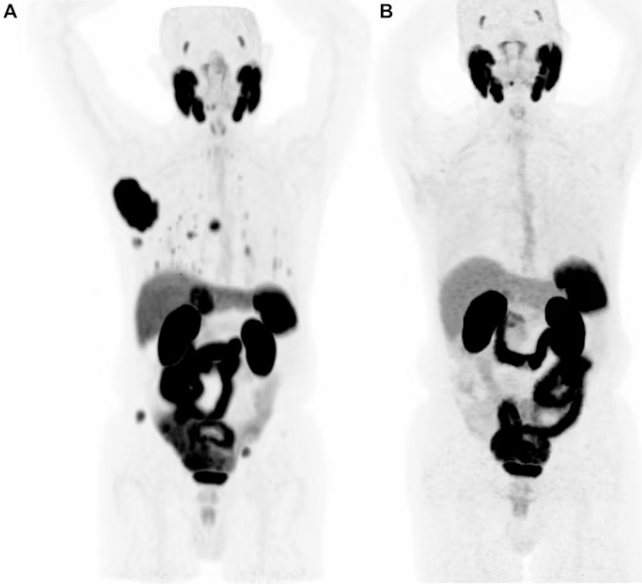

Ga-68 PSMA-PET/CT显示免疫检查点抑制剂治疗的完全应答接受阿替利珠单抗和贝伐珠单抗治疗的83岁男性转移性HCC患者的最大密度投影(MIP)图像。(A)基线预处理图像显示肝右叶有一个大的、强烈的psma摄取病灶,以及整个腹部和骨骼的多个转移病灶。(B)治疗开始后4个月的随访扫描显示所有肝内和肝外疾病的PSMA摄取完全消退。 |

7例患者(53.8%;10个病灶)接受了局部区域治疗(LRT), 6例患者(46.2%;19个病灶)接受了免疫检查点抑制剂(ICI)治疗。在约8周内,患者再次接受了PSMA-PET扫描,以及增强CT和MRI扫描。

2020年7月至2023年12月,研究者前瞻性纳入了符合本研究纳入标准的13例初治HCC患者。基线镓-68 (Ga-68) PSMA-11 PET/CT扫描(Biograph Vision 600, Siemens Healthineers; Discovery MI, GE HealthCare)确定了总共29个psma热衷的靶病变(中位病灶大小:2.1 cm)。